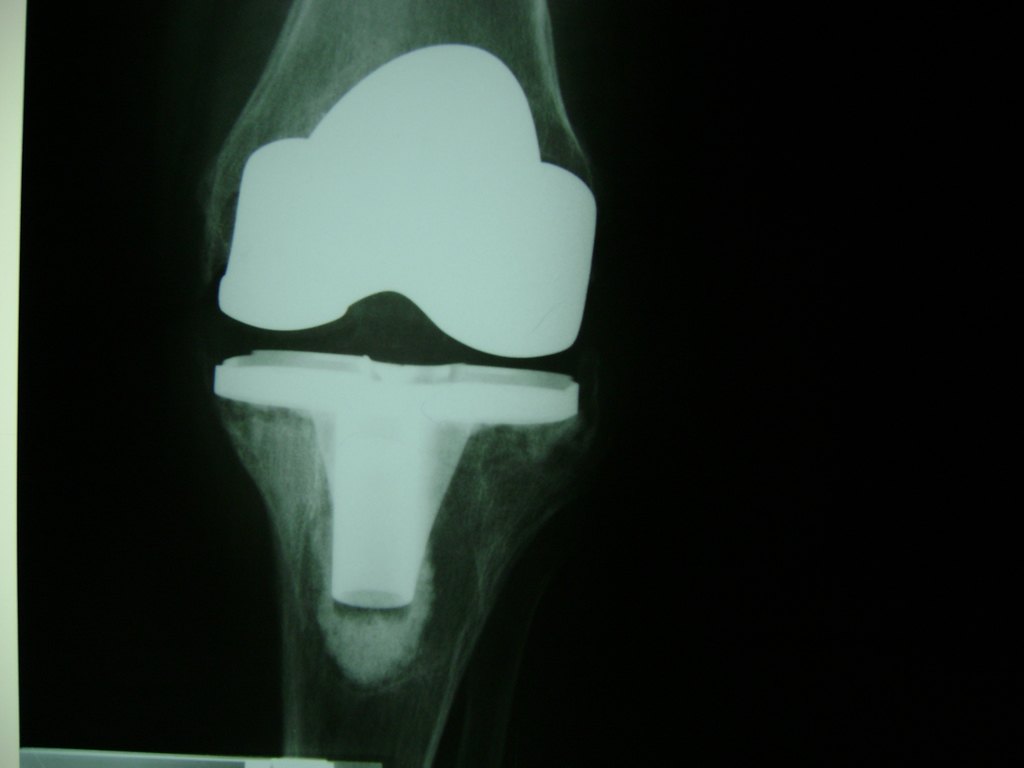

Cirugía de Rodillas